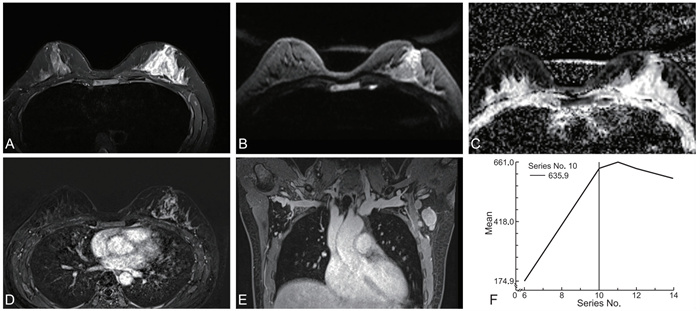

Correlation between MRI imaging characteristics of non-mass-like breast cancer and Ki-67 expression levels in non-mass breast cancer

XU Ling, ZHAO Hong, GONG Xijun, ZOU Liwei, WANG Longsheng

2025, 23(11): 1915-1919. doi: 10.16766/j.cnki.issn.1674-4152.004259

1632 1

Abstract:

Objective  To investigate the correlation between MRI features of non-mass breast cancer and Ki-67 expression, providing a basis for non-invasive preoperative assessment of tumor proliferative activity.  Methods  From January 2020 to December 2023, fifty-one patients with pathologically confirmed non-mass breast cancer were enrolled at the Second Affiliated Hospital of Anhui Medical University. Based on postoperative pathology, they were stratified into a low Ki-67 expression group (n=15) and a high-expression group (n=36). Comparisons included clinical data and MRI features [mean apparent diffusion coefficient (ADC) value, axillary lymph node metastasis, enhancement distribution, internal enhancement pattern, time-intensity curve (TIC) curve].  Results  No significant differences were observed in age, mean ADC value, enhancement distribution, or internal enhancement between groups (P>0.05), with clustered ring enhancement predominating (47.06%, 24/51). The high-expression group showed significantly higher axillary lymph node metastasis rates than the low-expression group [58.33%(21/36) vs. 26.67% (4/15), P=0.041].TIC curves in the high Ki-67 group were categorized as type Ⅰ (1 case), type Ⅱ(15 cases), and type Ⅲ (20 cases), while the low Ki-67 group showed type Ⅰ (3 cases), type Ⅱ (9 cases), and type Ⅲ (3 cases). TIC distribution differed significantly between groups (P=0.018), with statistically significant differences in Ki-67 expression between type Ⅰ and Ⅲ curves (Bonferroni-corrected, P < 0.017). Axillary lymph node metastasis rate positively correlated with Ki-67 expression (Kendall' s tau-b=0.289, P=0.041). mean ADC value negatively correlated (r=-0.334, P=0.017), and TIC curve type positively correlated (r=0.303, P=0.031). The combined AUC of axillary lymph node metastasis and TIC curves for predicting Ki-67 expression was 0.761 (sensitivity 0.861, specificity 0.667), outperforming individual indicators (AUC: 0.658, 0.678).  Conclusion  Non-mass breast cancer frequently exhibits clustered ring enhancement. Axillary lymph node metastasis and TIC curves correlate with Ki-67 expression, and their combination improves predictive efficacy, offering value for preoperative assessment of tumor proliferative activity.